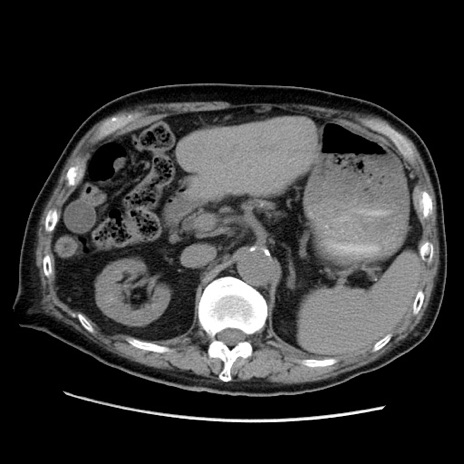

症例21(横断像)

【症例】70歳代男性

【主訴】腹痛

【現病歴】肝硬変・肝細胞癌にてかかりつけの方。約9時間前に食後より腹痛出現。症状が徐々に増悪し、嘔吐出現したため来院。

【既往歴】肝硬変、肝細胞癌(RFA、TACE後)

【身体所見】意識清明、表情苦悶様、BT 36℃、BP 129/78mmHg、P 88bpm、SpO2 97%(RA)、右上腹部から心窩部にかけて圧痛あり、反跳痛なし、筋性防御あり。

【データ】WBC 5800、CRP 0.16